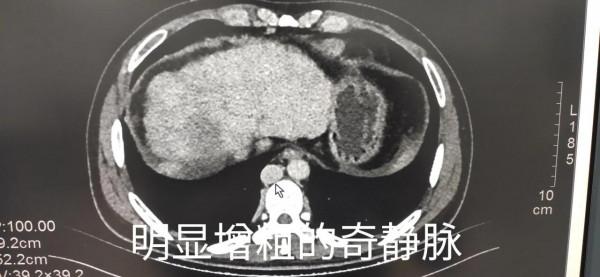

患者遂入院行上腹部多期增強CT檢查,發現肝右葉低密度病變邊緣部可見動脈期團片狀輕度不均勻強化,門脈期及延遲期基本呈等密度。憑經驗此病變高度懷疑肝癌,但又不十分典型,遂與臨床醫生溝通,然而反饋的結果是病人並沒有肝炎病史,查血甲胎蛋白結果未出。當時心裡就產生了大大的疑問,患者年紀輕輕,又沒有肝炎,怎麼會這麼嚴重的肝硬化,並且出現非常可疑的腫瘤病變呢?突然意識到另外一個徵象,就是平掃時就發現的異常增粗的奇靜脈,當時以為只是肝硬化門脈高壓側支迴圈形成造成的結果。但透過增強影象可以看到,食管胃底靜脈曲張並不明顯,而腰背部及腎臟周圍可見多發迂曲增粗的靜脈血管,最終都匯入到奇靜脈造成其異常粗大。當時就想到了一個病——布加綜合徵,觀察病人的下腔靜脈肝內段顯影模糊,肝上段下腔靜脈區域性狹窄,顯示不清。繼續追問病史,患者自述兩年前就有小腿間斷反覆潰瘍伴色素沉著(由於某種原因,沒有留下照片)。